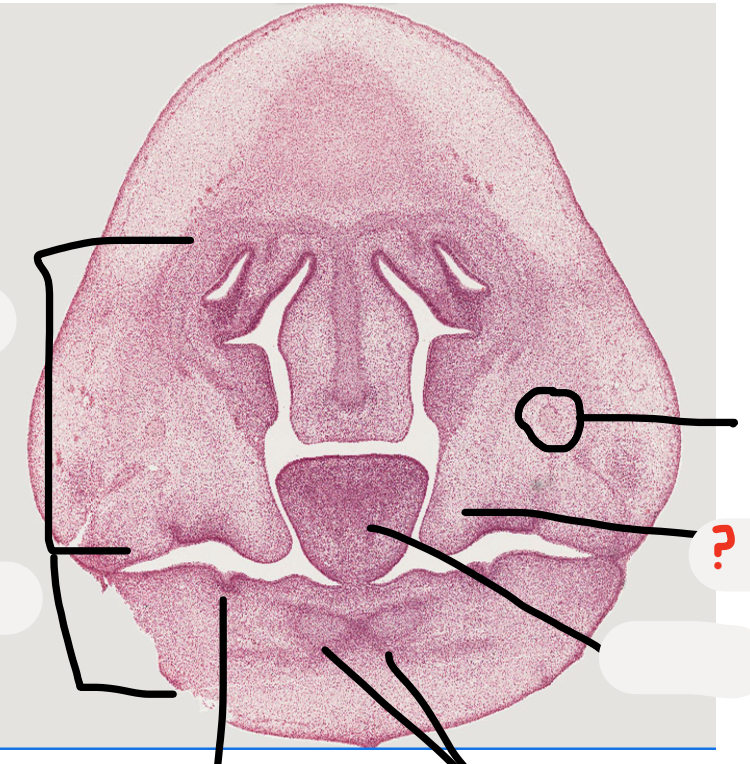

Not at all

what age is this specimen? why?

A

Week 8, palatal shelves elevated but not fused yet

palatal shelves

tooth germ

meckel's cartilage

developing mandible

inferior alveolar nerve

this will be the sulcus